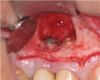

Report of a case. A 45-year-old male patient was referred with pain, redness, and swelling around an implant in the position of the maxillary right second premolar. The implant had been in clinical function for 3 years. The patient had a history of endodontic treatment and tooth loss and subsequent implant treatment in the region. Radiographic examination showed a radiolucency around the apical portion of the implant and the adjacent tooth. The implant was clinically stable and the neighboring tooth No. 4 was considered to have a periapical lesion. Initially, the patient received antibiotics (clindamycin 300 mg, three times daily) and was followed up for 2 weeks. After this, the patient was scheduled for surgical exploration of the implant area. Treatment comprised elevation of a full-thickness flap, curettage of the apical lesion, irrigation with saline, and removal of the apical portion of the implant and apicoectomy of the adjacent tooth (Figure 3 and Figure 4), including a guided bone regeneration (GBR) procedure with a cancellous particulate allograft and 20 mm x 30 mm pericardium membrane. Granulation tissue was sent for histopathology analysis, which revealed a periapical inflammatory infection. At the 4-month follow-up increased radiographic bone density could be observed consistent with the formation of bone not only around the implant apex but also along the root of tooth No. 5 (Figure 5).

Fig 3. Intraoperative radiograph demonstrating apical resection of implant and tooth.

Figure 3

Fig 4. Intraoperative situation after apical resection of implant and tooth.

Figure 4